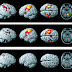

Visual memory fMRI task: between-groups T2 versus T1 ANOVA ...

Visual memory fMRI task: between-groups T2 versus T1 ANOVA ... from www.researchgate.net